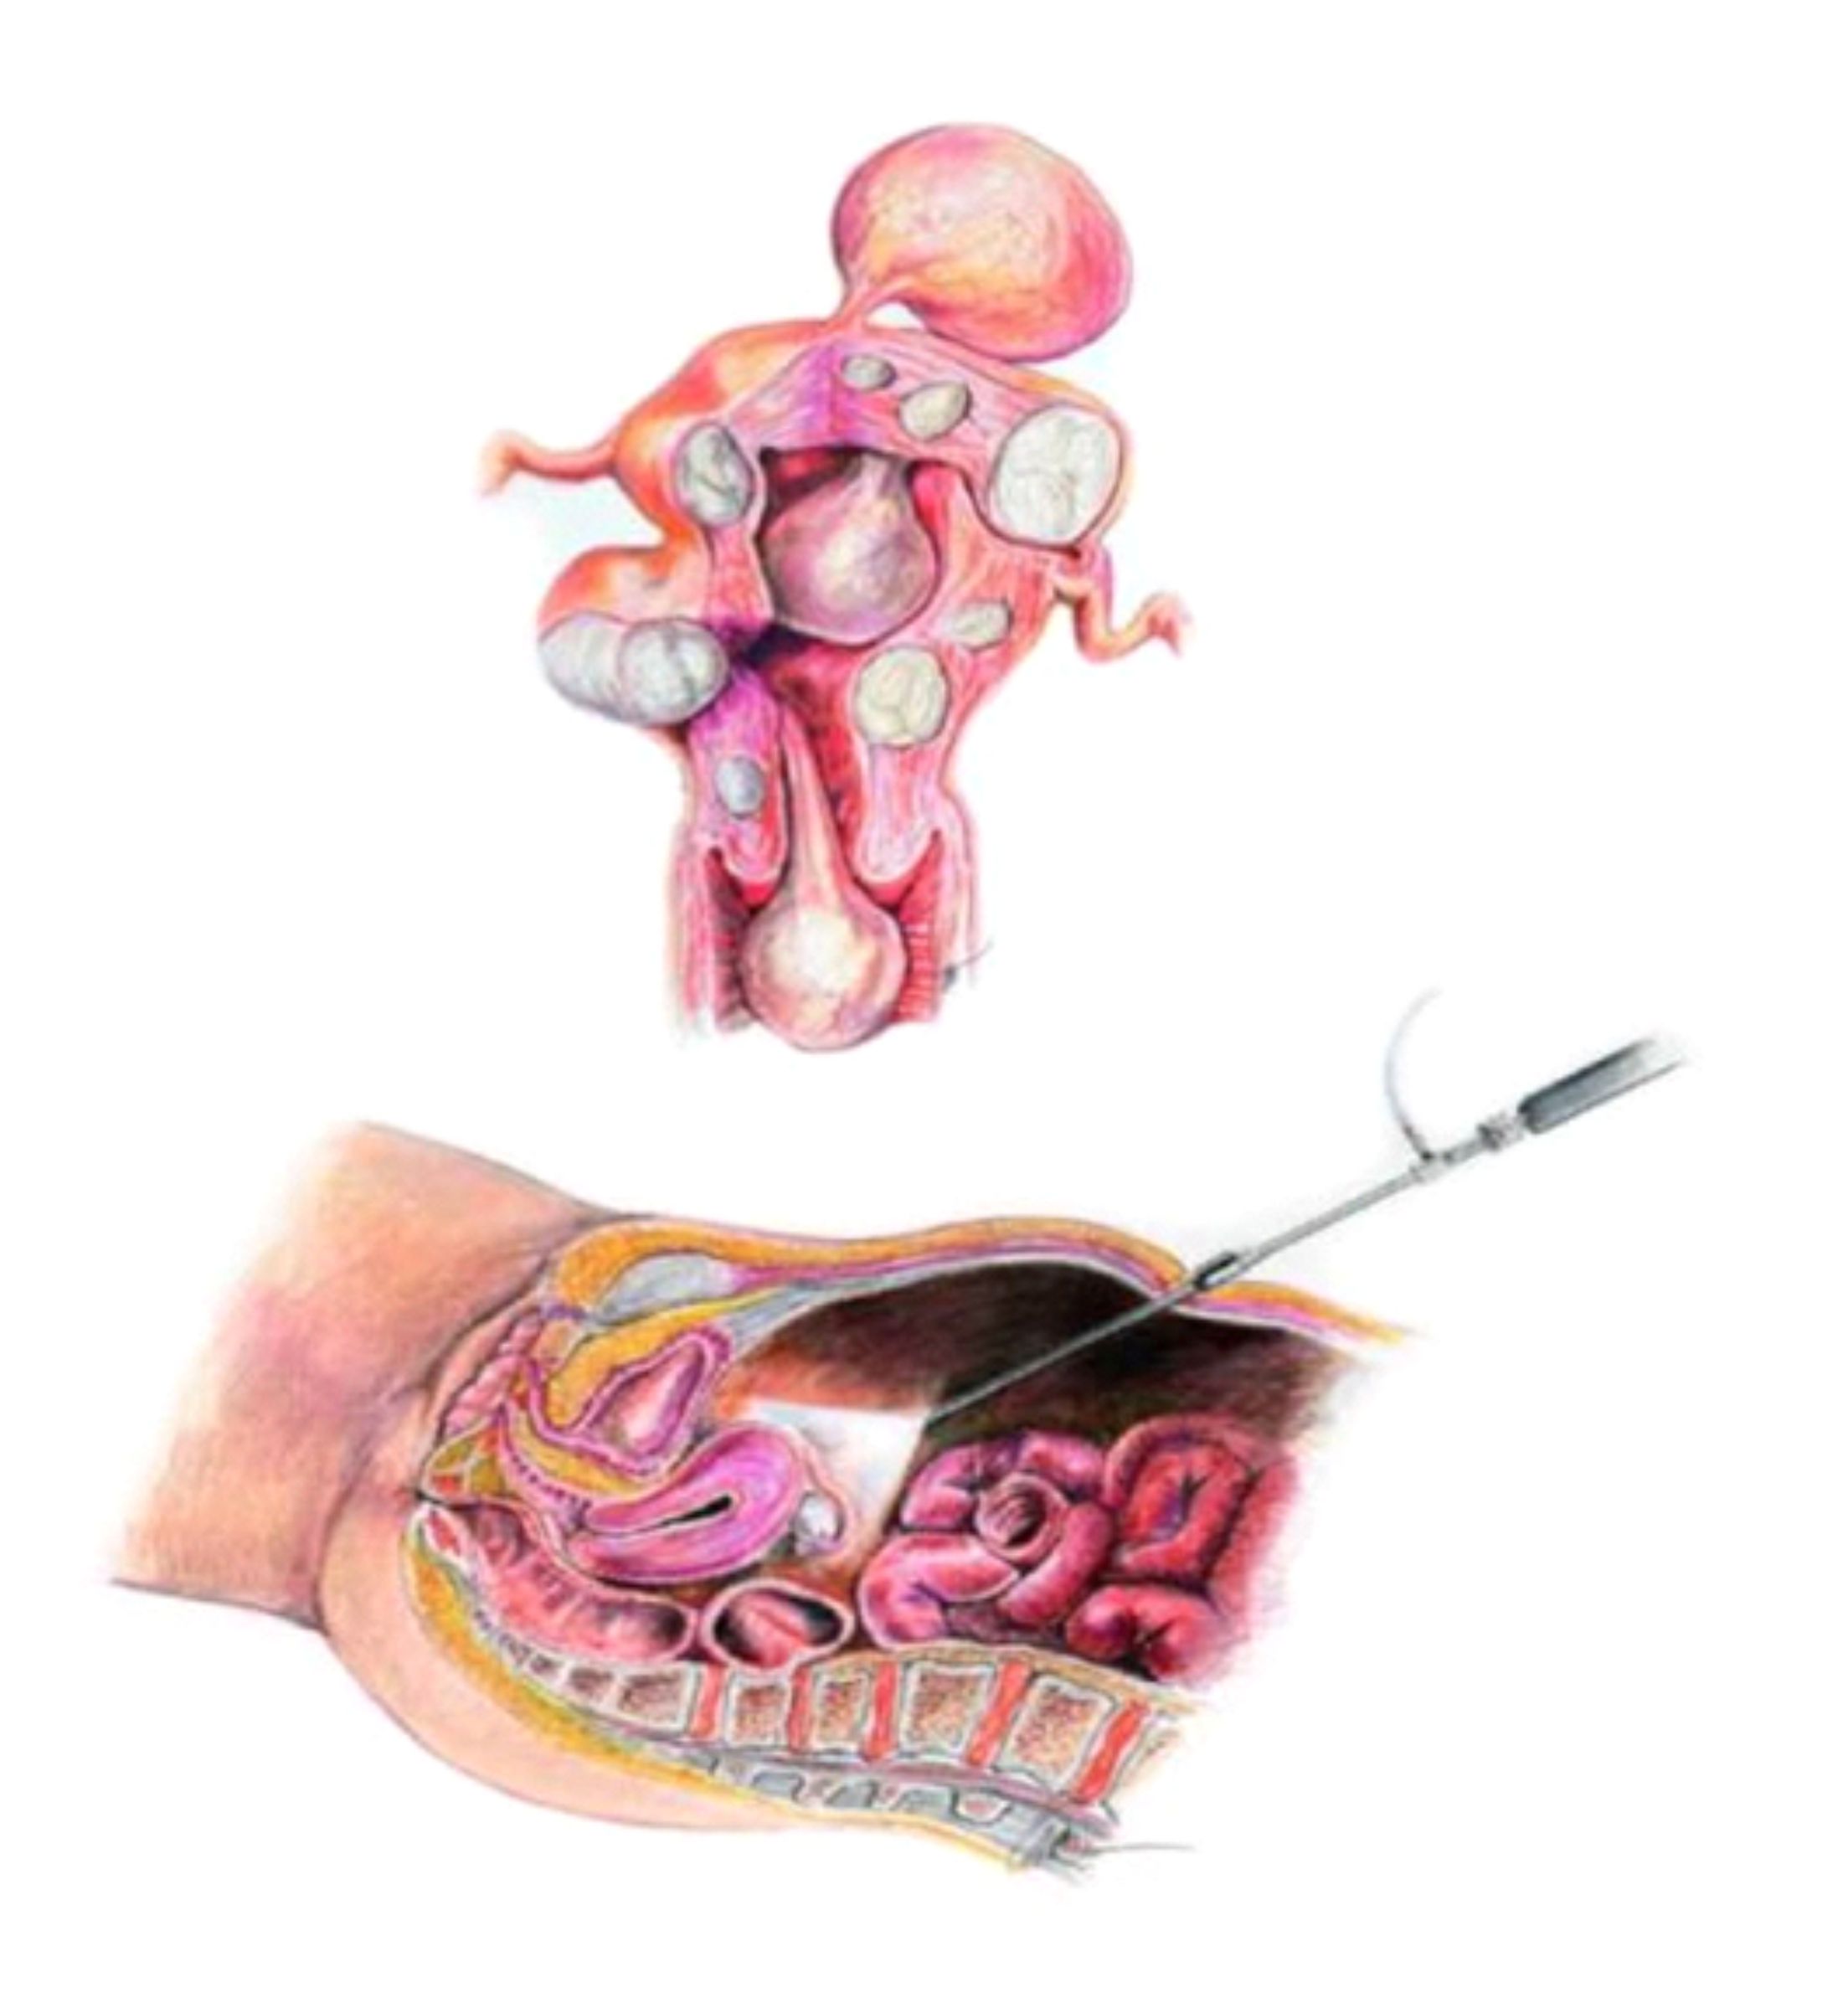

Visando uma melhor definição do tratamento, prognóstico e seguimento da endometriose, ao longo dos anos foram sendo propostas diferentes classificações da doença de acordo com a localização das lesões, o grau de comprometimento dos órgãos e sua severidade. Por muito tempo a classificação mais aceita foi a da American Fertility Society que divide a doença em mínima, leve, moderada e severa, sendo inclusive ainda adotada por muitas clínicas. Entretanto, estudos recentes tem recomendado uma nova classificação com melhor associação entre clínica e estadiamento e relação com a fisiopatogenia. Essa nova classificação divide a endometriose em 3 tipos distintos: endometriose superficial, endometriose ovariana e endometriose profunda.

Apesar dos três tipos serem endometriose, são consideradas doenças diferentes, não possuem a mesma origem e portanto, recebem tratamentos diferenciados. Esta divisão tem facilitado o tratamento e a cura, e mostra a importância do médico especialista em conhecer cada um dos detalhes que envolvem a doença.

Endometriose ovariana é um tipo de endometriose que se apresenta como endometriomas, ou seja, cistos no ovário com conteúdo líquido achocolatado, que variam de tamanho, podendo atingir grandes volumes. Acometem 17% a 44% das pacientes com endometriose. Em cerca de 98,9% dos casos apresentam outro foco de endometriose, estando normalmente associados a aderências ao peritônio posterior e uma chance aumentada de endometriose intestinal. Podem ser bilaterais, mas, ocorrem mais frequentemente no ovário esquerdo.

É caracterizada pelo comprometimento mais profundo dos tecidos (acima de 0,5 cm), podendo involver intestinos, bexiga, ureteres e septo reto-vaginal (espaço entre reto, o útero e a vagina). A endometriose infiltrativa é a que mais causa dor e interferência no funcionamento dos órgãos. Com isso, sua evolução pode ser até comparada com a de um câncer – com a diferença de não levar à morte. É a que apresenta sintomatologia mais agressiva comprometendo o bem-estar e a qualidade de vida das pacientes, além de interferir na fertilidade mesmo quando são usadas as técnicas de Reprodução Assistida.